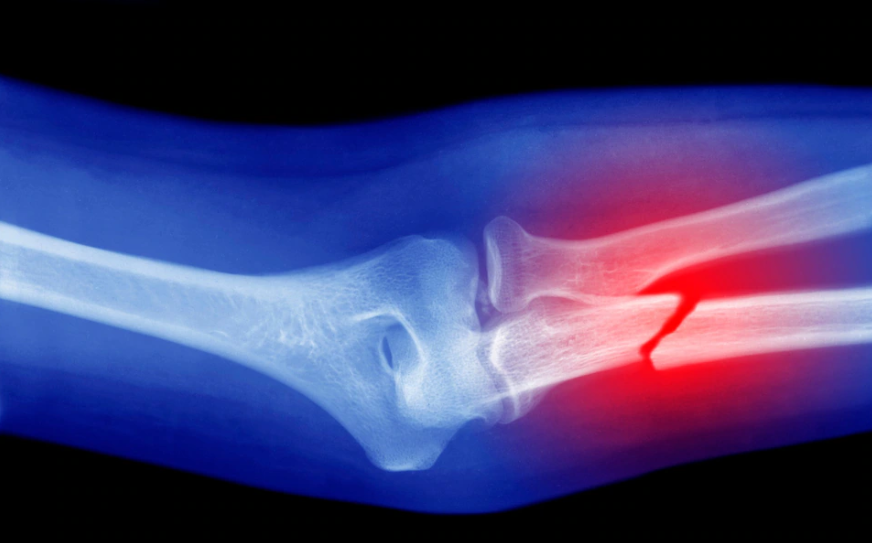

سيقوم الذكاء الاصطناعي بتشخيص الكسور بموجب خطط جديدة من هيئة الصحة الوطنية البريطانية (NHS)، حيث سيتم مراجعة الأشعة السينية للمرضى الذين يصلون إلى قسم الطوارئ مع اشتباه في وجود كسور بواسطة آلة، وفقاً للمقترحات الواردة في الإرشادات الأولية التي نُشرت يوم الثلاثاء.

سيتمكن موظفو قسم الطوارئ من استخدام الذكاء الاصطناعي لتسريع التشخيص وتقليل عدد الكسور التي لم يتم تشخيصها، وهي الأخطاء التشخيصية الأكثر شيوعًا في أقسام الطوارئ.

تشير الإرشادات إلى أن حوالي 3 إلى 10 في المائة من الكسور تُفوت في الرعاية العاجلة، بسبب الضغط على الأطباء الذين لا يتخصصون في الأشعة.

وقال المعهد الوطني للتميز في الرعاية الصحية (Nice) إن هناك أدلة كافية تُظهر أن الذكاء الصناعي أفضل من الأطباء في قسم الطوارئ عند تشخيص الكسور أو العظام المكسورة.